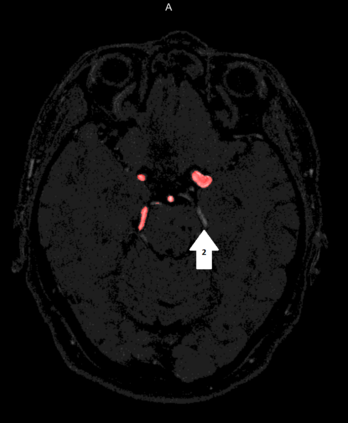

Deep learning approaches may help radiologists in the early diagnosis and timely treatment of cerebrovascular diseases. Accurate cerebral vessel segmentation of Time-of-Flight Magnetic Resonance Angiographs (TOF-MRAs) is an essential step in this process. This study investigates deep learning approaches for automatic, fast and accurate cerebrovascular segmentation for TOF-MRAs. The performance of several data augmentation and selection methods for training a 2D and 3D U-Net for vessel segmentation was investigated in five experiments: a) without augmentation, b) Gaussian blur, c) rotation and flipping, d) Gaussian blur, rotation and flipping and e) different input patch sizes. All experiments were performed by patch-training both a 2D and 3D U-Net and predicted on a test set of MRAs. Ground truth was manually defined using an interactive threshold and region growing method. The performance was evaluated using the Dice Similarity Coefficient (DSC), Modified Hausdorff Distance and Volumetric Similarity, between the predicted images and the interactively defined ground truth. The segmentation performance of all trained networks on the test set was found to be good, with DSC scores ranging from 0.72 to 0.83. Both the 2D and 3D U-Net had the best segmentation performance with Gaussian blur, rotation and flipping compared to other experiments without augmentation or only one of those augmentation techniques. Additionally, training on larger patches or slices gave optimal segmentation results. In conclusion, vessel segmentation can be optimally performed on TOF-MRAs using a trained 3D U-Net on larger patches, where data augmentation including Gaussian blur, rotation and flipping was performed on the training data.